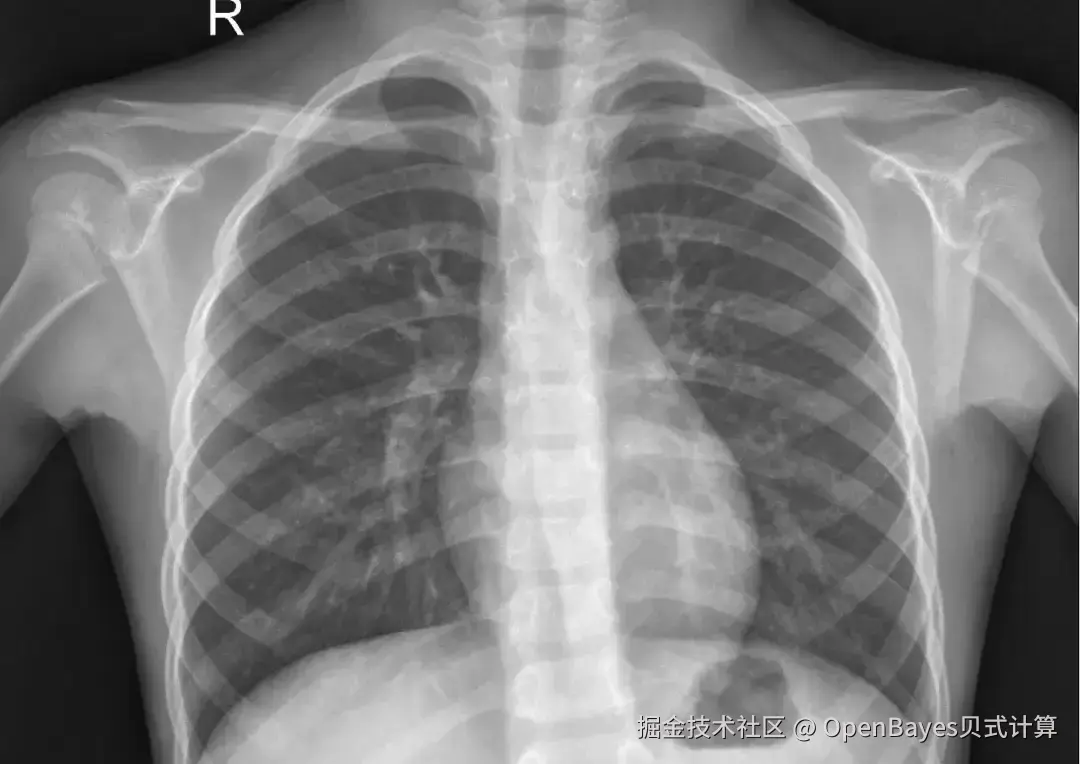

• X-ray 胸部肺炎 X 光图像数据集

1. X-ray 胸部肺炎 X 光图像数据集

X-Ray Images for Chest Pneumonia 数据集包含约 5,800 张胸部 X 光图像,分为正常和肺炎(细菌性和病毒性)两类。该数据集包含 2 个类别的图像:肺炎(Pneumonia)图像和正常(Normal)图像。

数据集示例